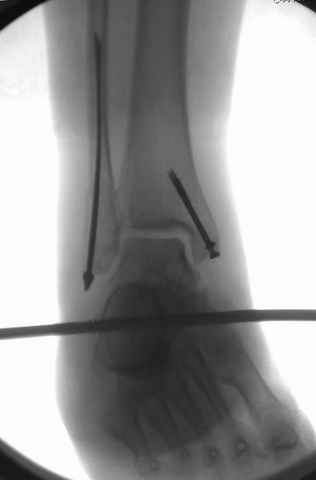

Второй случай сделан из одного разреза

ЕЧ LISS plate, mininvasive approach - luxurous !

Вопрос практического характера - такой подход рутинный или при определенных показаниях и каких? Спрашиваю потому, что при потоке больных - закрытая голень, бедро, голеностоп и т.д. лучевая нагрузка должна быть немалая, каковы показатели дозиметра после такого операционного дня и при 2-3 операционных днях в неделю по 5-6 случаев (не считая ургентностей)?

С точки зрения : Сгорая сам - свети другим :-)) это вполне понятно, но личная практика показывает, что далеко не все пациенты относятся волнительно и критично к длине кожного разреза. Подозреваю, что это и есть критерий при выборе техники фиксации?

На прямой проекции послеоперационного Рг макроскопически все выглядит очень анатомично, при микроскопическом ( :-)) ) рассмотрении можно все-таки заметить вальгизацию тарана, суставная щель в латеральном отделе сустава несколько уже , чем в медиальном при отсутствии латерального смещения тарана. У меня был аналогичный случай (без LISS , без мини доступа) с вальгусным наклоном тарана при восстановленном ankle mortise при последовательном наблюдении с интервалами в 6-8 недель в послеоперационном периоде отмечалось прогрессирующее сужение суставной щели в латеральном отделе сустава, закончившееся посттравматическим ОА, к счастью боли умеренные, купируемые аналгетиками или своими эндорфинами:-))(активная пациентка, у которой нет времени на болезни....) Какова жизненная ситуация в приведенном вами случае? И последнее, что я хотел бы прояснить для себя - фиксация внутренней лодыжки: я обычно комбинирую фиксацию компрессирующим винтом со спицей - по идее ротационная стабильность должна быть лучше, чем один винт, каковы ваши наблюдения в этом плане?